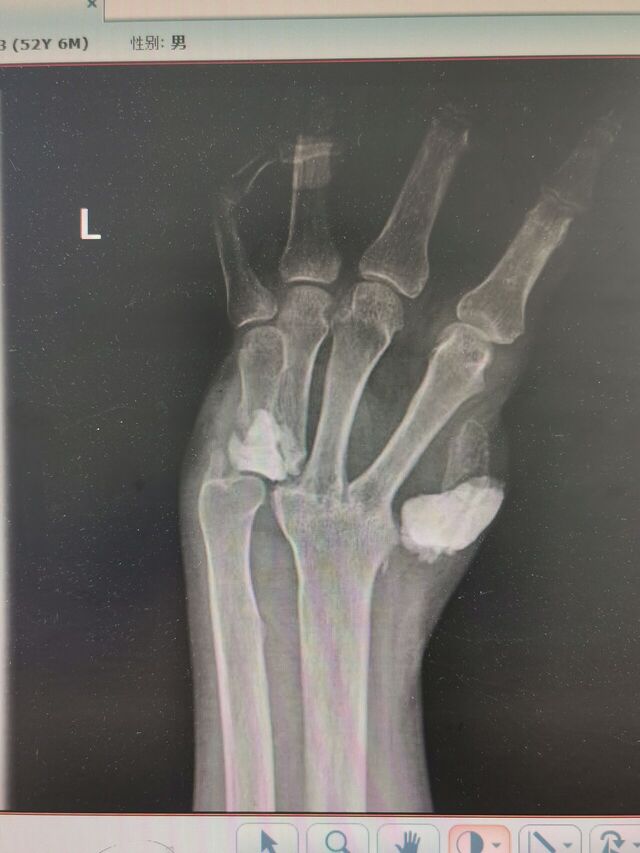

明天一台S-K手术

患者是断腕再植术后

旋转功能受限

活动范围旋前30°-0-0°旋后